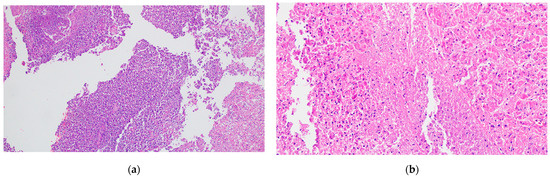

- Centro-acinar cells—delimiting the lumen together with acinar cells; they are small, flattened, or cuboidal in shape; the cytoplasm is pale, and the nucleus is oval; these cells are considered reserve cells for acinar and ductal cells (see Figure 4a).

- Intralobular ducts—represented by intercalated ducts that continue the lumen of the acini and are delimited by simple cuboidal epithelium; intercalated ducts fuse to form proper intralobular ducts, which are larger and delimited by simple cuboidal or columnar epithelium; around these ducts, a loose connective stroma can be observed, with numerous reticulin fibers, yet quantitatively reduced overall; unlike major salivary glands, the exocrine pancreas does not have striated ducts (see Figure 4a,b).